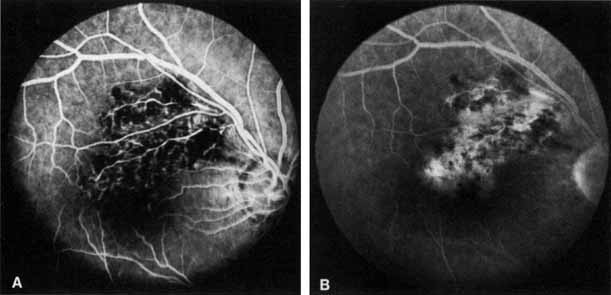

Fig. 2 A. Nonischemic central retinal vein occlusion. Note venous engorgement, dot, blot, and flame-shaped hemorrhages, blurring of disc margins, and a hemorrhage overlying the macula. B. Fluorescein angiogram reveals mild venous engorgement and tortuosity with virtually no capillary nonperfusion.

The ophthalmoscopic features of nonischemic central retinal vein occlusion are similar to those of ischemic central retinal vein occlusion, but are much less extensive (see Fig. 2; Fig. 3A and 3B). Engorgement of the venous tree (including the capillaries) is prominent; there is increased tortuosity and dilation and a darker appearance of the blood column. Retinal hemorrhages vary markedly. Sometimes they occur only peripherally; at other times, they may be rather prominent in the posterior pole.60 Cotton-wool spots are rare. Vision may be decreased because of macular edema or macular hemorrhage.

Fig. 3 A and B. Acute nonischemic central retinal vein occlusion in a 36-year-old hypertensive man. His visual acuity was 20/200. C and D. Six weeks later, he presented with eye pain, decreased vision, and neovascular glaucoma. The type of occlusion now is ischemic.